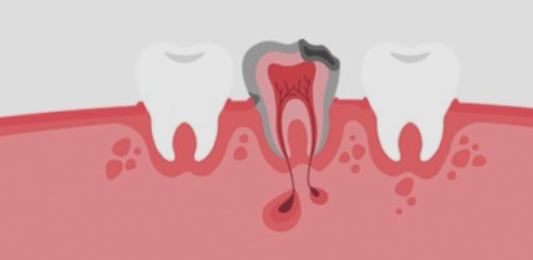

외상 또는 충치로 인해 치아의 치수(신경)가 손상되었거나 염증이 생기게되면 통증이 느껴지게 되요. 문제가 생긴 신경을 방치하게 되면 일상생활에 지장이 있을 정도로 통증이 심해지며 염증이 점점 커지기 때문에 손상되었거나 염증이 생긴 치수를 제거하는 것이 치아 신경치료이에요.

치아 신경치료 후 뿌리 끝에 염증이 생기며 통증이 나타나는 경우도 있어요. 신경치료가 잘 되었음에도 뿌리끝에 염증이 생기는 경우가 있는데요, 이는 복잡한 구조로 제거할 수 없는 근관속 염증이 뿌리끝에 모이게 되면서 잇몸이 부었다 가라앉았다를 반복하는 경우, 통증이 생기는 경우 등의 증상이 생기게 되며 치료방법으로는 치아 재식술 or 임플란트를 통해 치아의 기능을 회복하기도 해요.